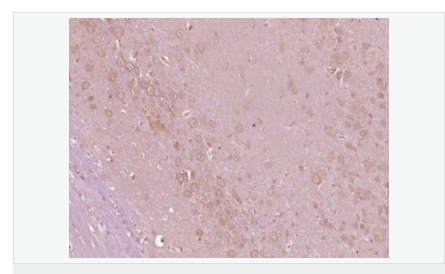

| 產(chǎn)品應(yīng)用 | ELISA=1:5000-10000 IHC-P=1:100-500 IHC-F=1:100-500 IF=1:100-500 (石蠟切片需做抗原修復(fù)) not yet tested in other applications. optimal dilutions/concentrations should be determined by the end user. |

| 產(chǎn)品介紹 | This gene encodes a cytoplasmic protein tyrosine kinase which is involved in calcium-induced regulation of ion channels and activation of the map kinase signaling pathway. The encoded protein may represent an important signaling intermediate between neuropeptide-activated receptors or neurotransmitters that increase calcium flux and the downstream signals that regulate neuronal activity. The encoded protein undergoes rapid tyrosine phosphorylation and activation in response to increases in the intracellular calcium concentration, nicotinic acetylcholine receptor activation, membrane depolarization, or protein kinase C activation. This protein has been shown to bind CRK-associated substrate, nephrocystin, GTPase regulator associated with FAK, and the SH2 domain of GRB2. The encoded protein is a member of the FAK subfamily of protein tyrosine kinases but lacks significant sequence similarity to kinases from other subfamilies. Four transcript variants encoding two different isoforms have been found for this gene. [provided by RefSeq, Jul 2008] Function: Non-receptor protein-tyrosine kinase that regulates reorganization of the actin cytoskeleton, cell polarization, cell migration, adhesion, spreading and bone remodeling. Plays a role in the regulation of the humoral immune response, and is required for normal levels of marginal B-cells in the spleen and normal migration of splenic B-cells. Required for normal macrophage polarization and migration towards sites of inflammation. Regulates cytoskeleton rearrangement and cell spreading in T-cells, and contributes to the regulation of T-cell responses. Promotes osteoclastic bone resorption; this requires both PTK2B/PYK2 and SRC. May inhibit differentiation and activity of osteoprogenitor cells. Functions in signaling downstream of integrin and collagen receptors, immune receptors, G-protein coupled receptors (GPCR), cytokine, chemokine and growth factor receptors, and mediates responses to cellular stress. Forms multisubunit signaling complexes with SRC and SRC family members upon activation; this leads to the phosphorylation of additional tyrosine residues, creating binding sites for scaffold proteins, effectors and substrates. Regulates numerous signaling pathways. Promotes activation of phosphatidylinositol 3-kinase and of the AKT1 signaling cascade. Promotes activation of NOS3. Regulates production of the cellular messenger cGMP. Promotes activation of the MAP kinase signaling cascade, including activation of MAPK1/ERK2, MAPK3/ERK1 and MAPK8/JNK1. Promotes activation of Rho family GTPases, such as RHOA and RAC1. Recruits the ubiquitin ligase MDM2 to P53/TP53 in the nucleus, and thereby regulates P53/TP53 activity, P53/TP53 ubiquitination and proteasomal degradation. Acts as a scaffold, binding to both PDPK1 and SRC, thereby allowing SRC to phosphorylate PDPK1 at 'Tyr-9, 'Tyr-373', and 'Tyr-376'. Promotes phosphorylation of NMDA receptors by SRC family members, and thereby contributes to the regulation of NMDA receptor ion channel activity and intracellular Ca(2+) levels. May also regulate potassium ion transport by phosphorylation of potassium channel subunits. Phosphorylates SRC; this increases SRC kinase activity. Phosphorylates ASAP1, NPHP1, KCNA2 and SHC1. Promotes phosphorylation of ASAP2, RHOU and PXN; this requires both SRC and PTK2/PYK2. Subunit: Homodimer, or homooligomer. Interacts with SIRPA and SH2D3C. Interacts with ARHGAP10. Interacts with DLG4 (By similarity). Interacts with NPHP1, ASAP1, ASAP2, ARHGAP26, SKAP2 and TGFB1I1. The Tyr-402 phosphorylated form interacts with SRC (via SH2 domain) and SRC family members. Forms a signaling complex with EPHA1, LCK and phosphatidylinositol 3-kinase; upon activation by EFNA1. Interacts with GRB2 (via SH2 domain). Interacts with P53/TP53 and MDM2. Interacts with MYLK. Interacts with BCAR1. Interacts with PDPK1. Interacts (hypophosphorylated) with PXN. Interacts with RB1CC1. Interacts with RHOU. Interacts with VAV1. Interacts with LPXN and PTPN12. Subcellular Location: Cytoplasm. Cytoplasm, perinuclear region. Cell membrane; Peripheral membrane protein; Cytoplasmic side. Cell junction, focal adhesion. Cell projection, lamellipodium. Cytoplasm, cell cortex. Nucleus. Note=Interaction with NPHP1 induces the membrane-association of the kinase. Colocalizes with integrins at the cell periphery. Tissue Specificity: Most abundant in the brain, with highest levels in amygdala and hippocampus. Low levels in kidney (at protein level). Also expressed in spleen and lymphocytes. Post-translational modifications: Phosphorylated on tyrosine residues in response to various stimuli that elevate the intracellular calcium concentration; this activation is indirect and may be mediated by production of reactive oxygen species (ROS). Tyr-402 is the major autophosphorylation site, but other kinases can also phosphorylate Tyr-402. Autophosphorylation occurs in trans, i.e. one subunit of the dimeric receptor phosphorylates tyrosine residues on the other subunit. Phosphorylation at Tyr-402 promotes interaction with SRC and SRC family members, leading to phosphorylation at Tyr-579; Tyr-580 and Tyr-881. Phosphorylation at Tyr-881 is important for interaction with GRB2. Phosphorylated on tyrosine residues upon activation of FGR and PKC. Recruitment by NPHP1 to cell matrix adhesions initiates Tyr-402 phosphorylation. In monocytes, adherence to substrata is required for tyrosine phosphorylation and kinase activation. Angiotensin II, thapsigargin and L-alpha-lysophosphatidic acid (LPA) also induce autophosphorylation and increase kinase activity. Phosphorylation by MYLK promotes ITGB2 activation and is thus essential to trigger neutrophil transmigration during lung injury. Dephosphorylated by PTPN12. DISEASE: Note=Aberrant PTK2B/PYK2 expression may play a role in cancer cell proliferation, migration and invasion, in tumor formation and metastasis. Elevated PTK2B/PYK2 expression is seen in gliomas, hepatocellular carcinoma, lung cancer and breast cancer. Similarity: Belongs to the protein kinase superfamily. Tyr protein kinase family. FAK subfamily. Contains 1 FERM domain. Contains 1 protein kinase domain. SWISS: Q14289 Gene ID: 2185 Database links: Entrez Gene: 2185 Human Entrez Gene: 19229 Mouse Omim: 601212 Human SwissProt: Q14289 Human SwissProt: Q9QVP9 Mouse Unigene: 491322 Human Unigene: 21613 Mouse Unigene: 11025 Rat Important Note: This product as supplied is intended for research use only, not for use in human, therapeutic or diagnostic applications. 富含脯氨酸的酪氨酸激酶 2 (protein richtyro sinekinase 2 ,PYK2 ) ,又稱細胞粘附激酶β(cellularadhesionkinaseβ ,CAKβ)、相關(guān)粘附聚焦酪氨酸激酶(relatedadhesionfocaltyrosinekinase ,RAFTK) ,是粘著斑激酶 (focaladhesionkinase,FAK)家族的成員之一。PYK2是FAK家族的成員之一 ,是一種鈣依賴性酪氨酸激酶 ,在氨基酸序列上與FAK有 4 5 %的同源性。它的活化涉及了多條信號傳導(dǎo)通路 ,與離子通道的調(diào)節(jié)、細胞骨架的聯(lián)系及細胞增殖、凋亡密切相關(guān)。血管緊張素Ⅱ、一氧化氮可調(diào)節(jié)PYK2的活性。在神經(jīng)系統(tǒng)中高度表達的蛋白酪氨酸激酶 (Pyk2),其酪氨酸殘基因為各種G蛋白偶聯(lián)受體和胞外信號而被磷酸化,從而增加胞內(nèi)鈣離子的濃度. |